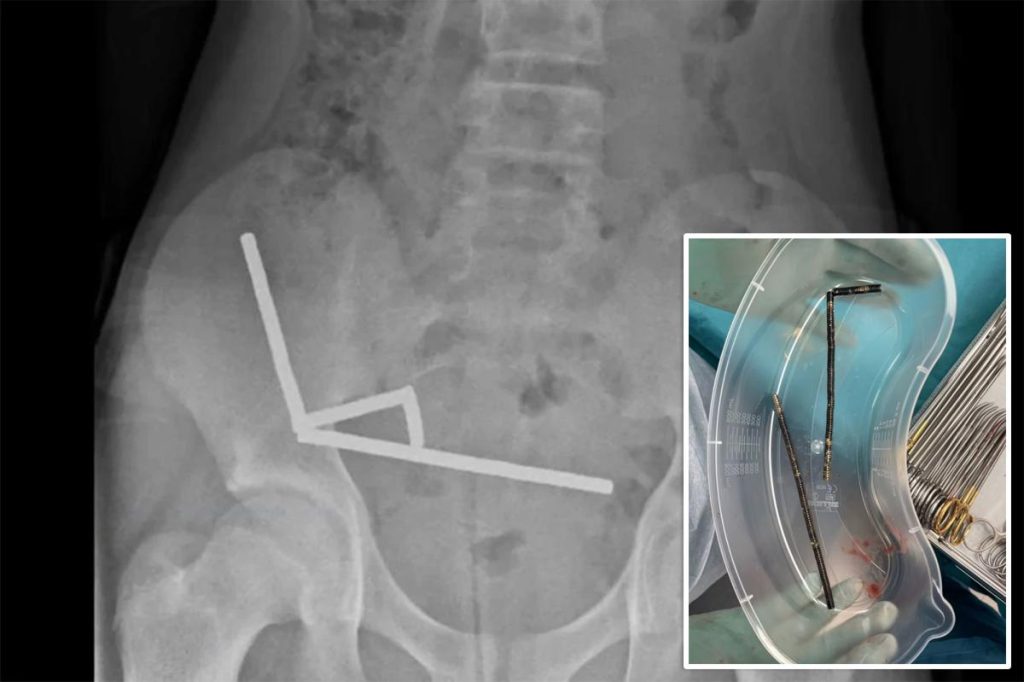

X-rays revealed 4 chains of magnets lodged in several sections of his intestines, pulling collectively and slicing off blood circulation to close by tissue.

He informed medical doctors he had ingested between 80 and 100 small neodymium magnets a couple of week earlier — however surgeons later recovered nearer to 200 from his intestine, in line with a case report printed Friday within the New Zealand Medical Journal.